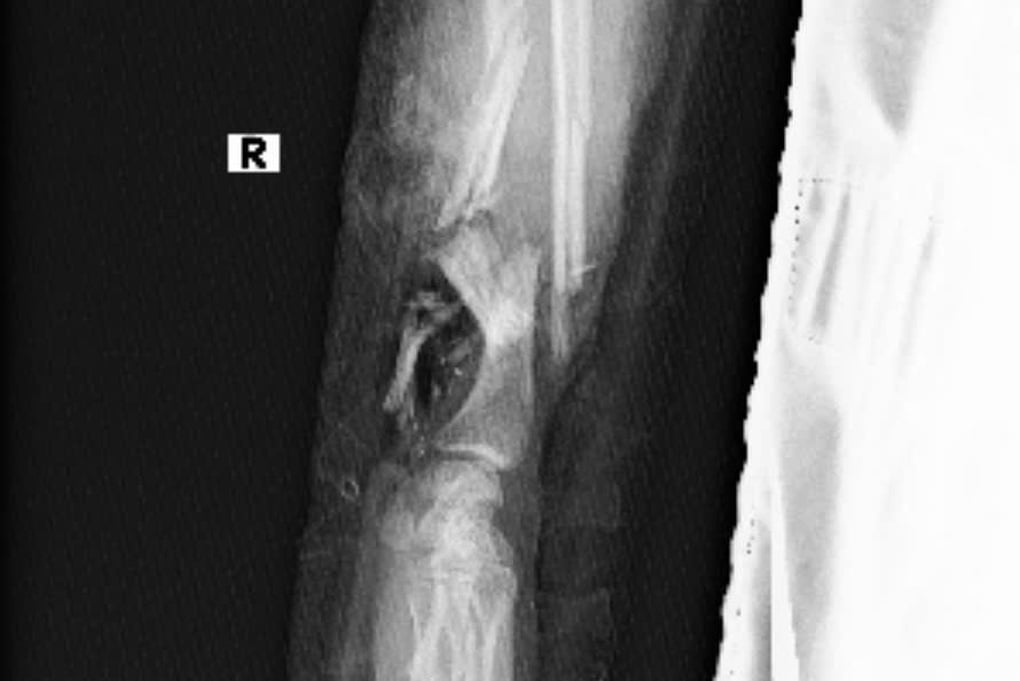

គ្រោះថ្នាក់នេះបណ្តាលឱ្យដៃស្តាំរបស់កុមារីរងរបួសបែកក្បាល(រូបថត៖ មន្ទីរពេទ្យ)

ដៃរបស់អ្នកជំងឺត្រូវបានគ្រូពេទ្យដាក់ជាបណ្ដោះអាសន្នលើជើងរបស់គាត់បន្ទាប់ពីការវះកាត់ដែលប្រើពេលជាច្រើនម៉ោង (រូបថត៖ មន្ទីរពេទ្យ)។

ការវះកាត់បានធ្វើឡើងនៅម៉ោង៥ល្ងាច។ និងបន្តរហូតដល់ម៉ោង ៣ ទៀបភ្លឺនៅថ្ងៃបន្ទាប់។ បច្ចុប្បន្នម្តាយ និងកូនទាំង២នាក់នៅមិនទាន់មានសុខភាពល្អទេ ចំណែកដៃបណ្តោះអាសន្នដែលប្តូរទៅជើងវិញគឺល្អ។ គេរំពឹងថានៅពេលដែលទារកឈានដល់អាយុ 32 សប្តាហ៍ គ្រូពេទ្យនឹងពិចារណាដាក់ដៃអ្នកជំងឺឡើងវិញ។